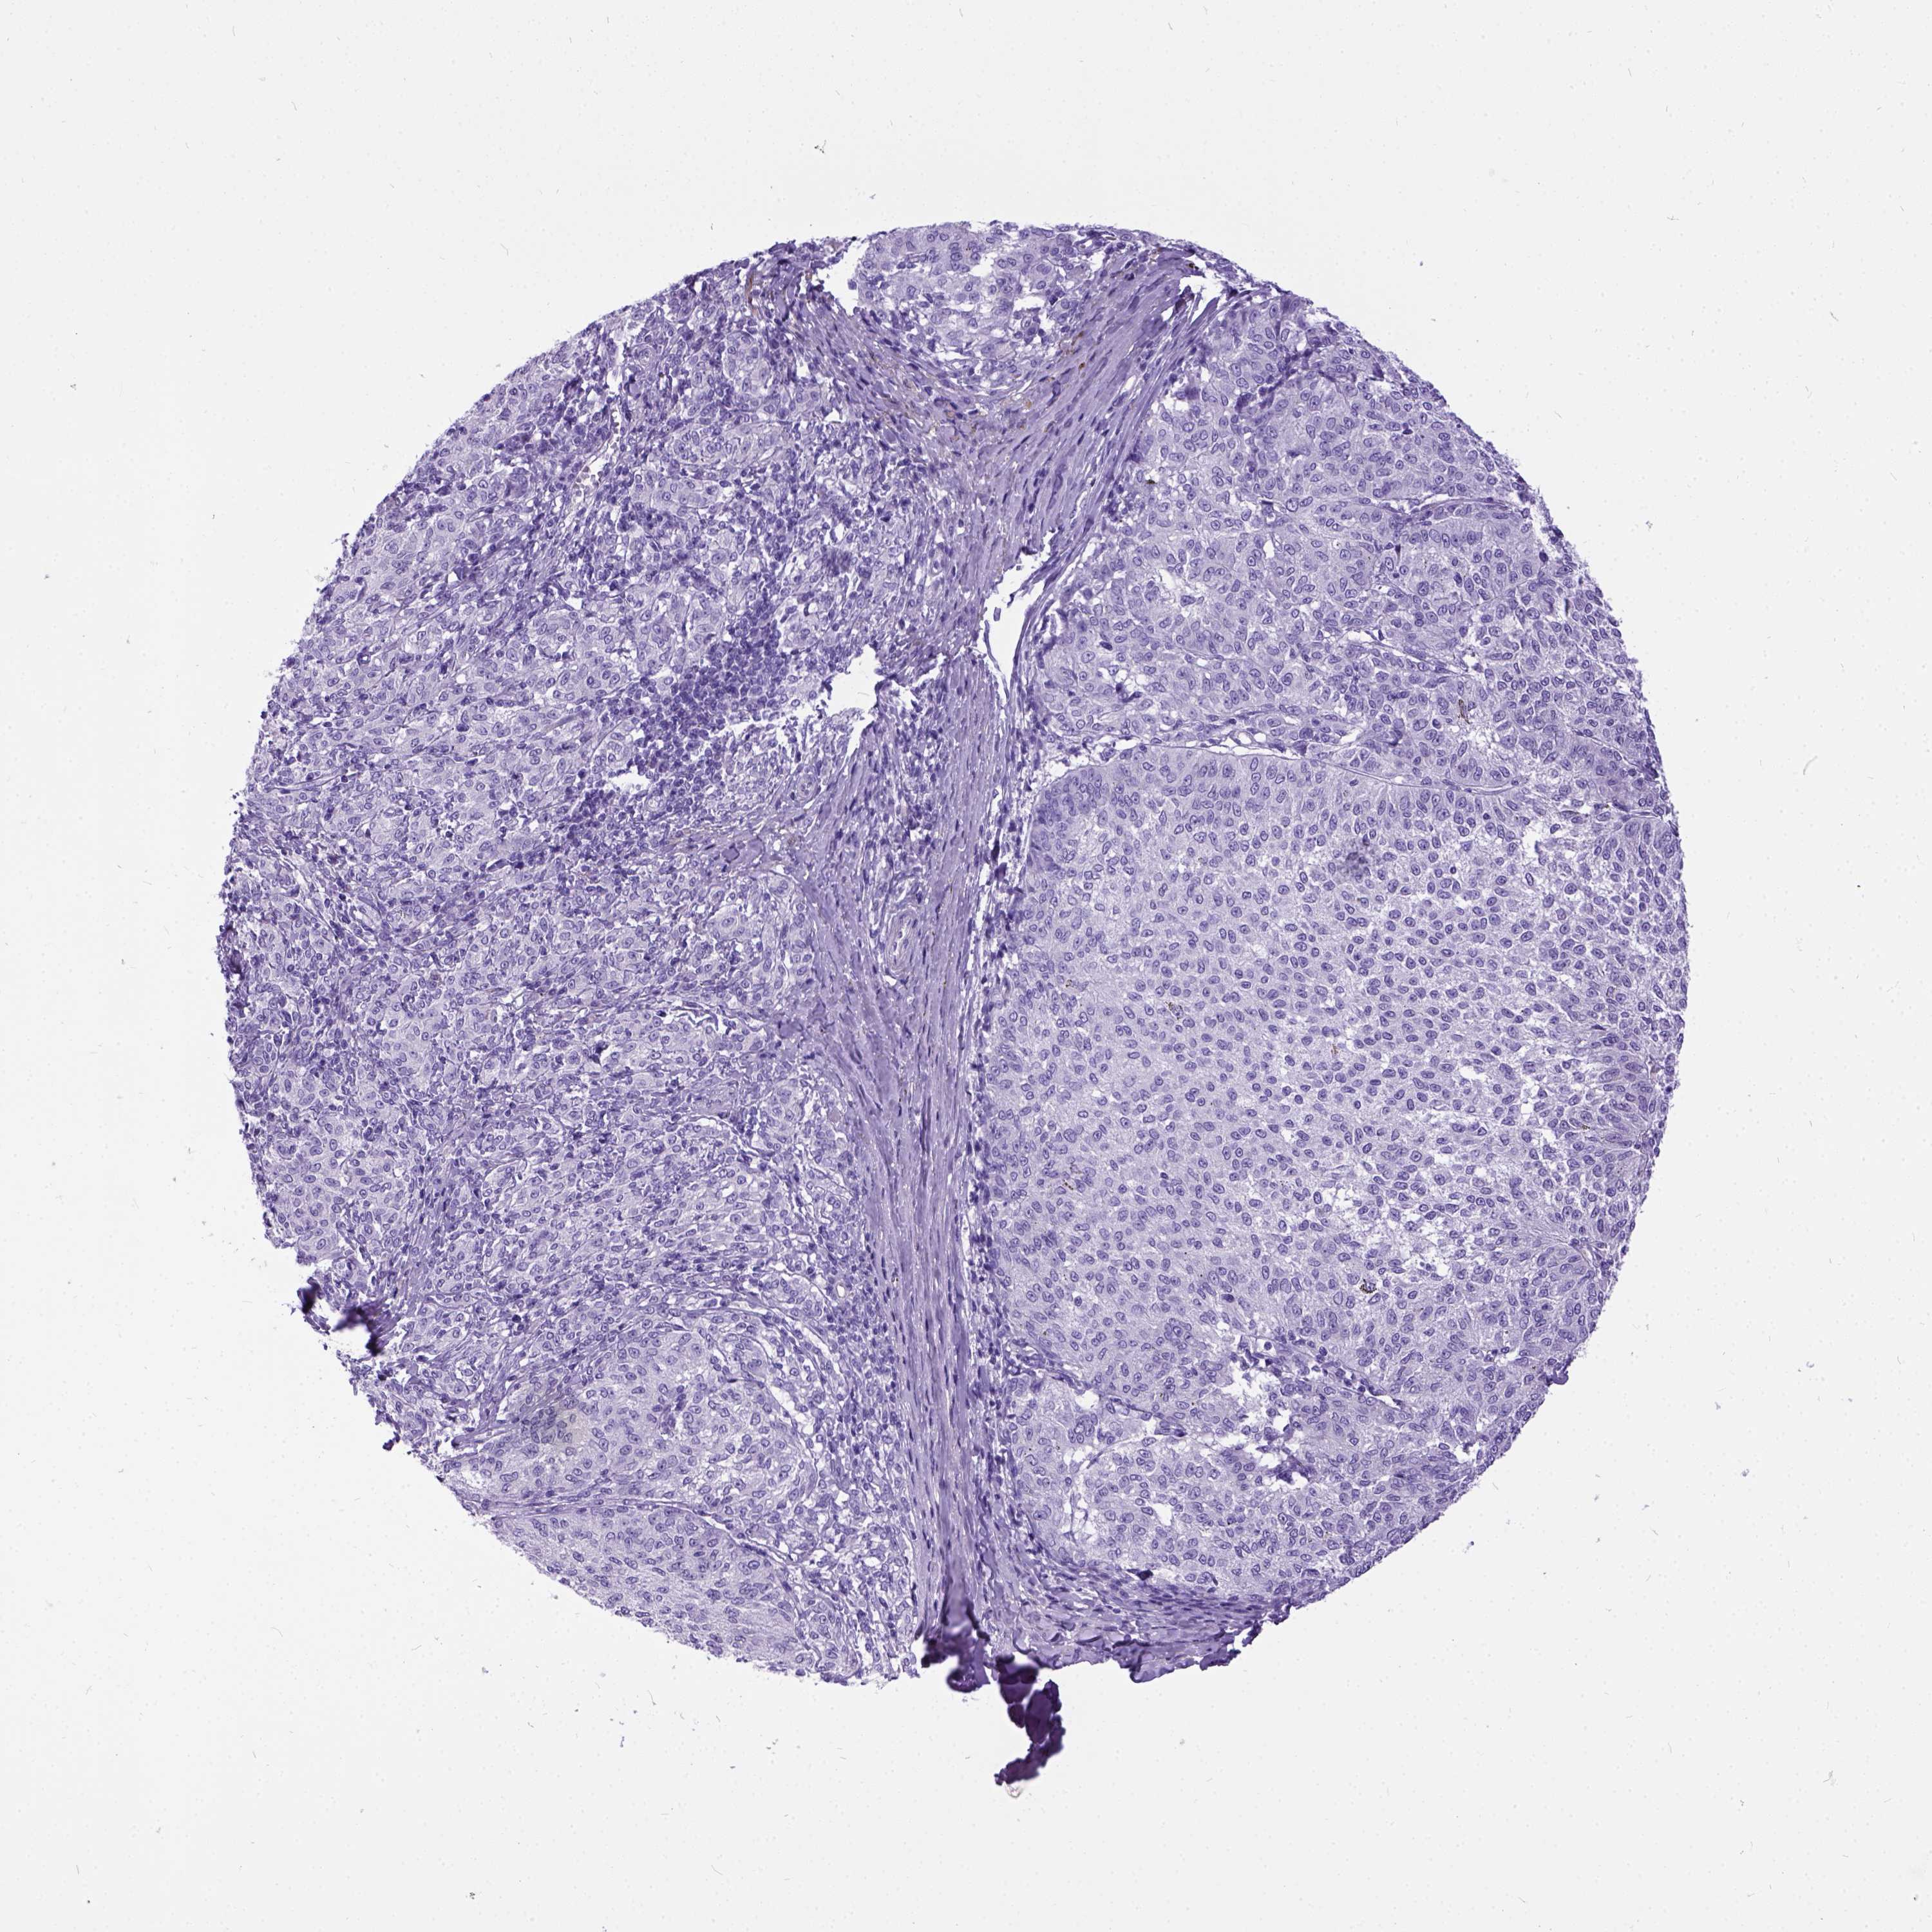

MELANOMA - Protein expressioni

A mouse-over function shows sample information and annotation data. Click on an image to view it in a full screen mode. Samples can be filtered based on level of antibody staining by selecting one or several of the following categories: high, medium, low and not detected. The assay and annotation is described here.

Note that samples used for immunohistochemistry by the Human Protein Atlas do not correspond to samples in the TCGA dataset.

Antibody stainingi

Antibody staining in the annotated cell types in the current human tissue is reported as not detected, low, medium, or high, based on conventional immunohistochemistry profiling in selected tissues. This score is based on the combination of the staining intensity and fraction of stained cells.

Each image is clickable and will lead to virtual microscopy that enables deeper exploration of all samples and also displays staining intensity scores, fraction scores and subcellular localization as well as patient and tissue information for each sample.

Antibody HPA007556

Staining

High

Medium

Low

Not detected

Intensity

Strong

Moderate

Weak

Negative

Quantity

>75%

75%-25%

<25%

None

Location

Nuclear

Cytoplasmic/membranous

Cytoplasmic/membranous,nuclear

Malignant melanoma, NOS

Malignant melanoma, Metastatic site